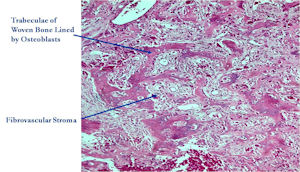

- Interlacing network of bone trabeculae in a loose fibrovascular stroma

- Prominent vessels

- Osteoblasts are plump, active, scattered mitotic figures

- Osteoblasts line up around periphery of trabeculae (Osteoblastic Rimming)

- Soft tissue component usually surrounded by shell of reactive bone or periosteum (Egg Shell Rim of Calcification)